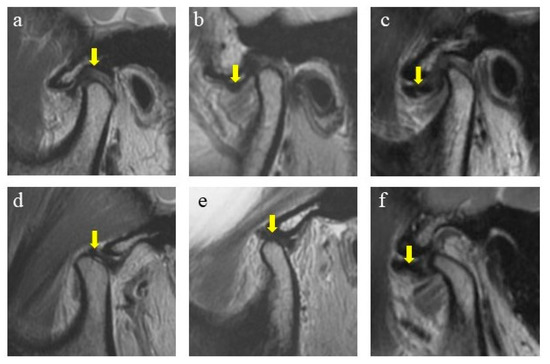

2.2. Magnetic Resonance Imaging (MRI) Evaluation

2.2.1. Normal Position

2.2.2. Disc Displacement with Reduction (DDwR)

2.2.3. Disc Displacement without Reduction (DDwoR)